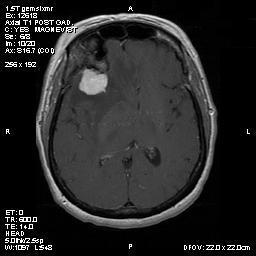

Clinical information The patient was a 54 year-old woman with a history of diabetes. She developed vomiting and frontal headache for two days. As per the descriptions of her family members, she had a few episodes of starring into the left and was unresponsive. The patient described that she could remember all these episodes clearly. On physical examination, the patient was well oriented and alert. There was no weakness in the extremities, ophthalmoplegia, diplopia, reduced visual acuity or facial weakness. An MRI and a CT scan were performed and yielded the following representative images. A surgery was performed. Representative photographs of the specimen are illustrated below.

T1-weighed MR images demonstrate an extraaxial, dural based mass involving the right supraorbital region  (Panel A and B). The mass shows homogeneous enhancement  (Panel C). CT scan demonstrates as well as rim calcification (Panel E). On T2-weighed imagers, significant vasogenic edema is demonstrated despite the small size of the lesion and the extraaxial location (Panel D).